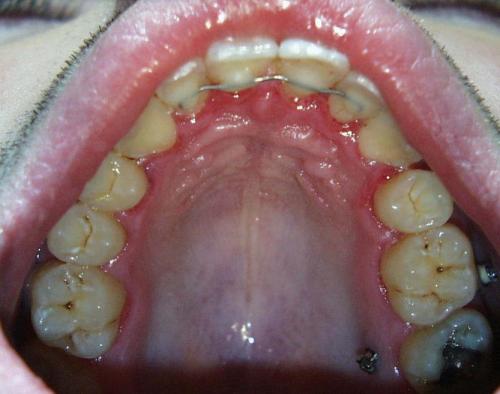

Nach der Behandlung

(Dauer der aktiven Behandlung: 1 Jahr, 11 Monate)

Eine langjährige Stabilisierung der Frontzähne mittels eines Kleberetainers ist unverzichtbar. Die Miniimplantate sind auf dem Foto unten links noch sichtbar; sie können bald nach dem Abnehmen der festen Zahnspange in einem kleinen chirurgischen Eingriff ebenfalls entfernt werden.